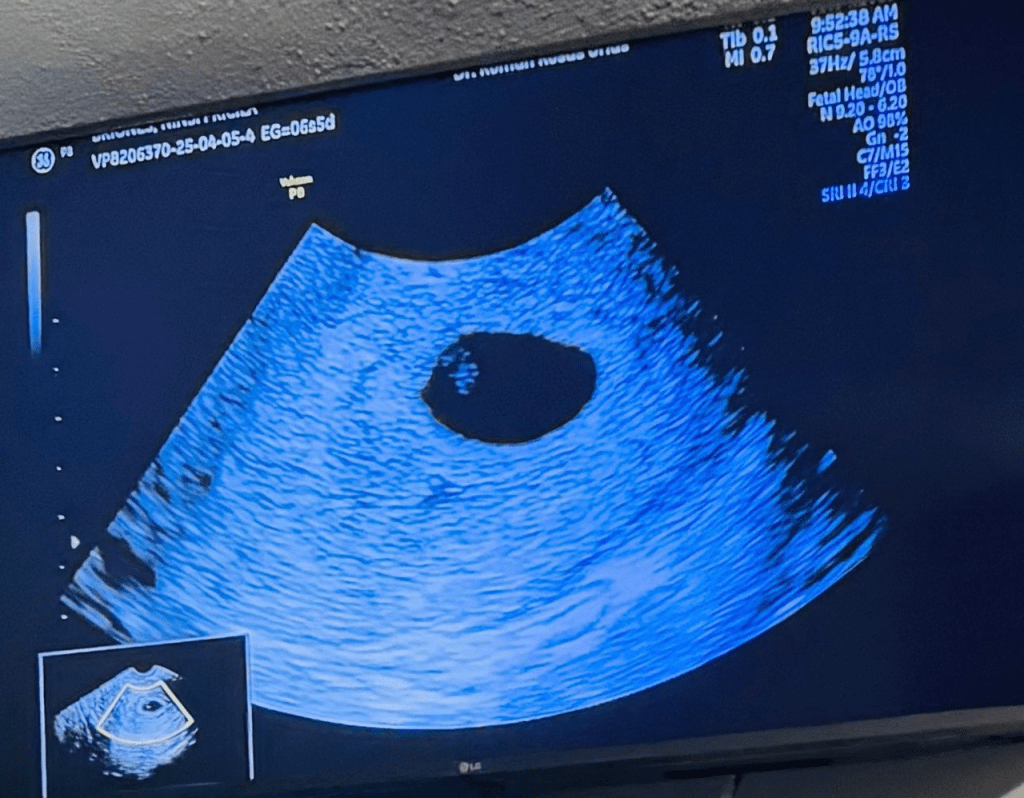

El sábado siguiente, durante la cita definitiva, el ultrasonido reveló un milagro: el embrión había crecido, su corazón latía con fuerza y todo indicaba que su embarazo avanzaba con normalidad.

Ecografía final con el bebé en la bolsa y todo normal.